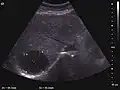

The ultrasound appearance is a well defined lesion, with very thin, almost unapparent walls, without circulatory signal at Doppler or CEUS investigation. The content is transonic suggesting fluid composition. The presence of membranes, abundant sediment or cysts inside is suggestive for parasitic, hydatid nature. Posterior from the lesion the acoustic enhancement phenomenon is seen, which strengthens the suspicion of fluid mass. They typically displace normal liver vessels but no vascular or biliary invasion occurs.

They can be single or multiple, with variable size, generally less than 20 mm (congenital). Rarely, sizes can reach several centimeters, leading up to the substitution of a whole liver lobe (acquired, parasitic). They may be associated with renal cysts; in this case the disease has a hereditary, autosomal dominant transmission (von Hippel Lindau disease).